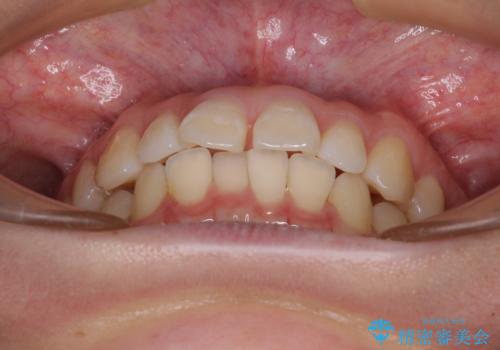

- 上顎前歯の隙間を気にして来院された患者様です。

下顎前歯が上顎前歯に食い込むような咬み合わせにより、上顎前歯が開いてしまっていたため、咬合高径の挙上により突き上げを改善するよう、インビザラインにより矯正治療を行うこととしました。